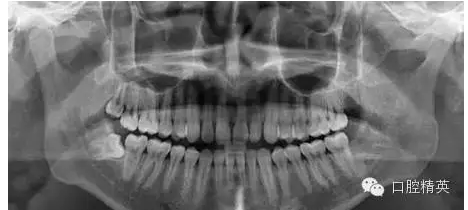

1、拔除前口內(nèi)全景片

7、拔牙后全景片